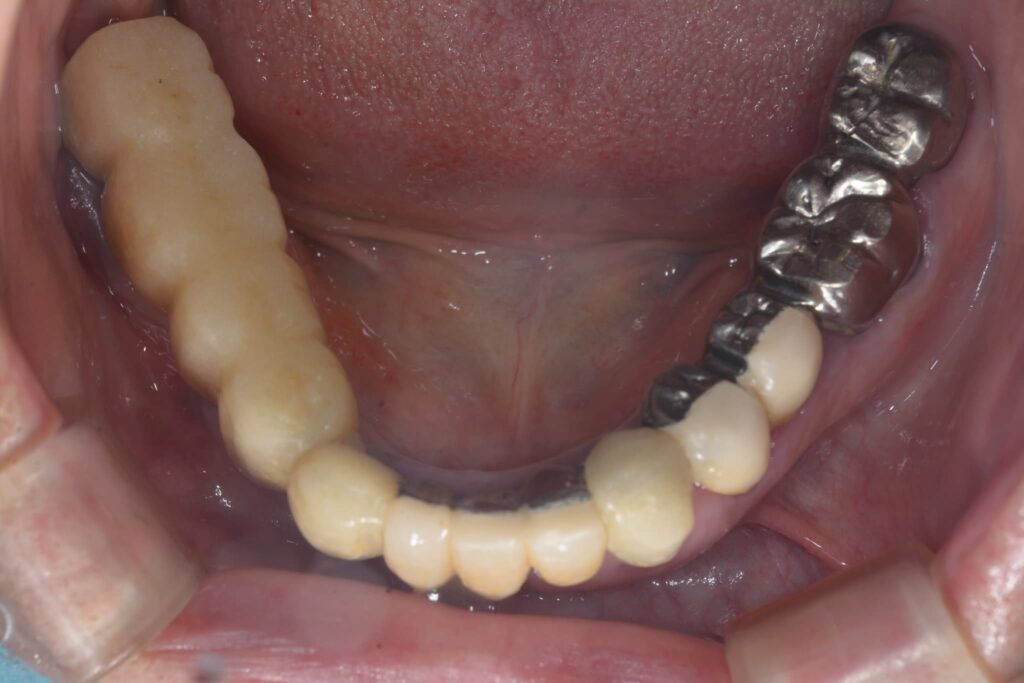

② 被せ物(上部構造)の破損・摩耗

インプラント本体(骨の中のネジ)に問題はなく、その上の人工の歯が欠けたり、すり減ったりしているケースです。

・修正方法: 型取りを行い、新しい被せ物を作り直すことで、噛み合わせと見た目を回復できます。この際、現在の噛み合わせの癖などを考慮し、より壊れにくい設計をご提案します。